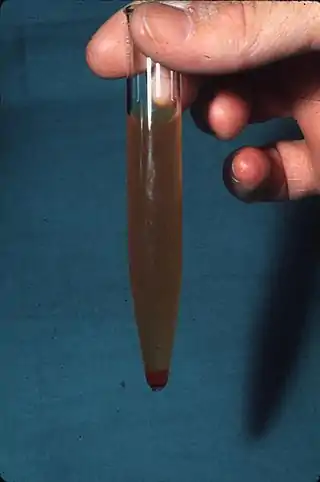

La hematuria es la presencia de sangre en la orina, una afectación frecuente en medicina humana. El color de la orina puede variar desde el color rojo sangre (o rojo vivo) hasta el color café (popularmente descrito como de bebida cola), dependiendo de si esta sangre es fresca o ha sido transformada en hemoglobina ácida por efecto del pH urinario.

Orina con hematuria macroscópica. | ||

La orina en condiciones normales no posee sangre. Se acepta como máximo un número de 1 o 2 hematíes por campo en el sedimento de orina centrifugada,[1] o hasta 5 hematíes por campo en mujeres. Lo cual no produce cambios en la coloración de la orina, dado que la sangre se torna macroscópica cuando hay 100 o más hematíes por campo en el mayor aumento.

- Hematuria macroscópica: la orina se observa de color rojiza. También denominada hematuria "franca" o "gruesa".